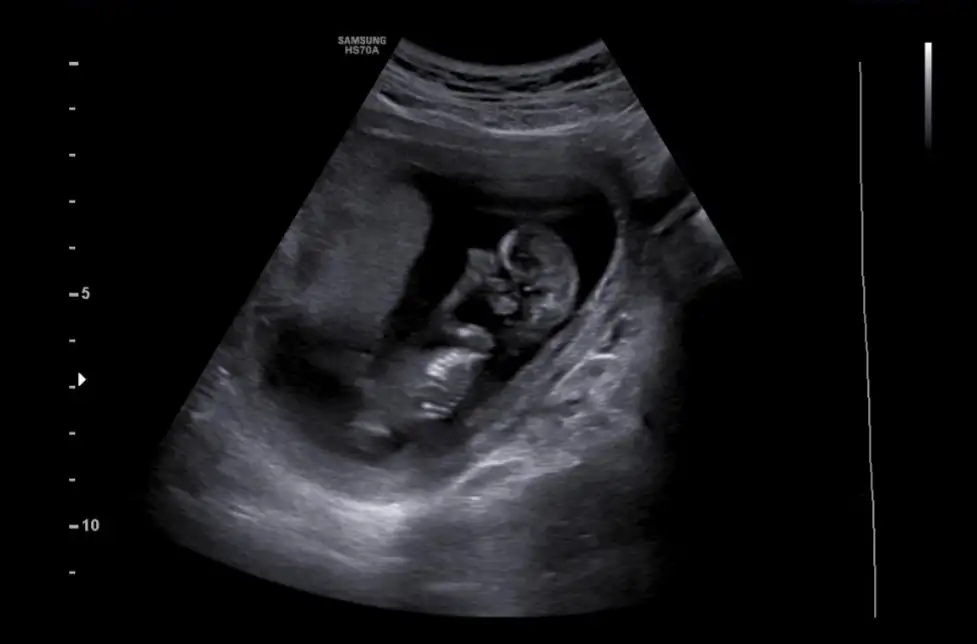

Merhaba bana da tahmin yapabilir misiniz?Erkek ve kız için 11 + 12+ yada 13 hafta usg görüntüsü olmalı açıklamalar asagıda yazıyorrabbim herkesin gönlüne göre nasip etsin inşallah .. ecmain

[/B]Eki Görüntüle 473828 gordugunuz gibi ust taraftaki simgedende anlasildigi gibi eger cikinti paralel ise kiz

yok 30°lik bir aciyla yukari dogru bakiyorsa %99 oglunuz olacak demektir simdi bi kac ornek resimler daha koyacagim kiziminkide dahil

Eki Görüntüle 473829 bu bir erkek bebek genital nub cikintisi gayet yukarda

Eki Görüntüle 473831 simdi burada cikintilara bakin eger bel popo cizgisine paralel ise kiz

yok 30 derecelik bir aciyla yukari bakiyorsa erkek

yabancilarin hepsi biliyor bunu biz neden eksik kalalim gayet bilimsel simdi ellerinde11 12 13 ultrason fotografi olanlar alsin hemen baksin yada koyalim buraya